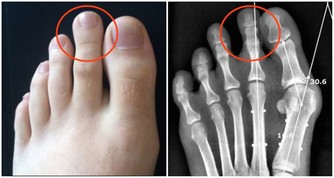

膝關節磨損不可修復

爬樓梯或爬山屬於負重運動,腰部以下的關節都要承受自己身體的重量,尤其膝蓋受力最多。

當身體爬階向上時,膝蓋負擔的重量會瞬間增為平常的4倍左右。

以一個體重60公斤的人為例:平路行走時,兩邊膝蓋各承重60公斤。

爬樓梯或爬山時,膝蓋負重瞬間變成240公斤,相當於左右膝蓋上各扛了一架鋼琴。

而且,這種對膝蓋的磨損是不可修復的!磨損如果過度嚴重,只能夠置換關節!

一方面我們需要鍛煉大腿和臀部的肌肉群。但是另一方面,我們又不能以傷害膝關節為代價,因為膝關節的壽命由基因決定,是60年,過度使用會加重對它的磨損,並且不可修復。

在爬山和爬樓梯的時候,膝關節會承受超過本身體重3到4倍的壓力。尤其是50歲以後,人的膝關節多少都會有些磨損的情況,此時,就要減少此類運動。對於有些有過膝關節損傷的朋友40歲以後就要特別注意了。